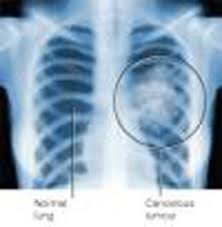

During physical tests for Mesothelioma lung cancer, the doctor may check breath sounds to see whether there is any indication of fluid in the chest cavity. A variety of diagnostic procedures also help to determine whether a patient has Mesothelioma lung cancer.

Results from imaging scans, tissue biopsies, pulmonary function tests, and other diagnostic techniques, combined with the findings from a careful medical history help to define the course of treatment in Mesothelioma lung cancer.